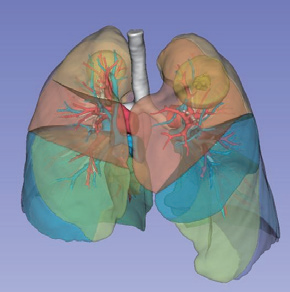

↑三维重建肺动静脉预览

↑三维重建肺动静脉及肺段整体预览

阿梵D可显示7-8级脉管

更直观的显示肺动脉流域

消除由于分段不准确造成的切除范围误导

减少分段误差,确保精细准确的手术规划

↑肺段体积评估分析